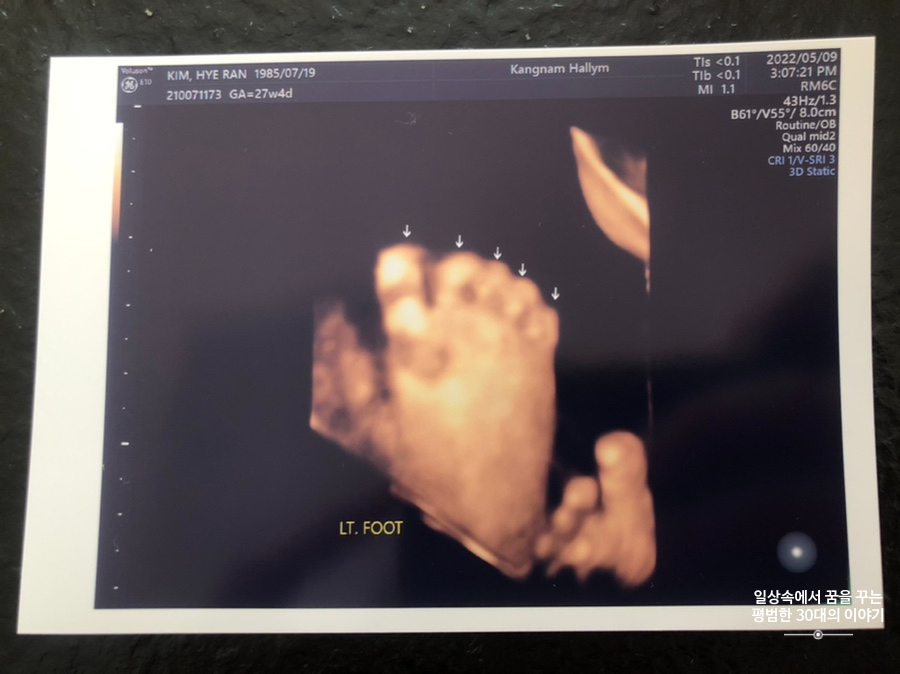

오늘은 입체 초음파 보는 날!!! 입체 초음파는 처음인데다 3주 만에 이안이 얼굴을 본다 생각하니 무척 설레는 마음으로 병원에 갔다. 첫 번째 시도에서는 계속 내 등 쪽으로 얼굴을 대고 엎드려 있어 실패! 초코우유 먹고 열심히 걸은 후, 30분 뒤에 다시 진행한 두 번째 시도에서는 얼굴 반쪽을 보여줬다. 얼굴 전면을 보지 못해 너무 아쉬웠지만 그래도 손가락 빨고 있는 모습, 웃고 있는 모습, 입 뻐끔 거리는 모습, 발차기 하는 모습, 손가락 쥐었다 폈다 하는 모습, 손을 휘적휘적 거리는 모습 등 다양한 모습을 보여줘서 그것만으로도 충분히 만족스러웠다. 내가 다니고 있는 강남성심병원은 입체 초음파가 다른 병원에 비해 무척 비싼 편인데(진료비 내역을 보니 초음파 진단료가 129800원 나옴) 그나마 위안을 삼을 수 있는 것은 화질이 그나마 좋은 편이라는 것이다.